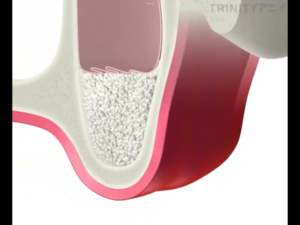

『サイナスリフトとは?』

下の図のように上顎の骨が少なく、副鼻腔との距離が近く骨を盛り上げる場合に選択する治療方法です。

歯茎を切開し、副鼻腔につながる骨を一部削除します。

副鼻腔内の粘膜を破らないように慎重に上方に持ち上げていきます。

それによってできた副鼻腔内の空洞に人工骨を填入します。

骨を盛り上げた部分にインプラントを埋入します。

この人工の骨が既存の骨と一体化するまで待機します。